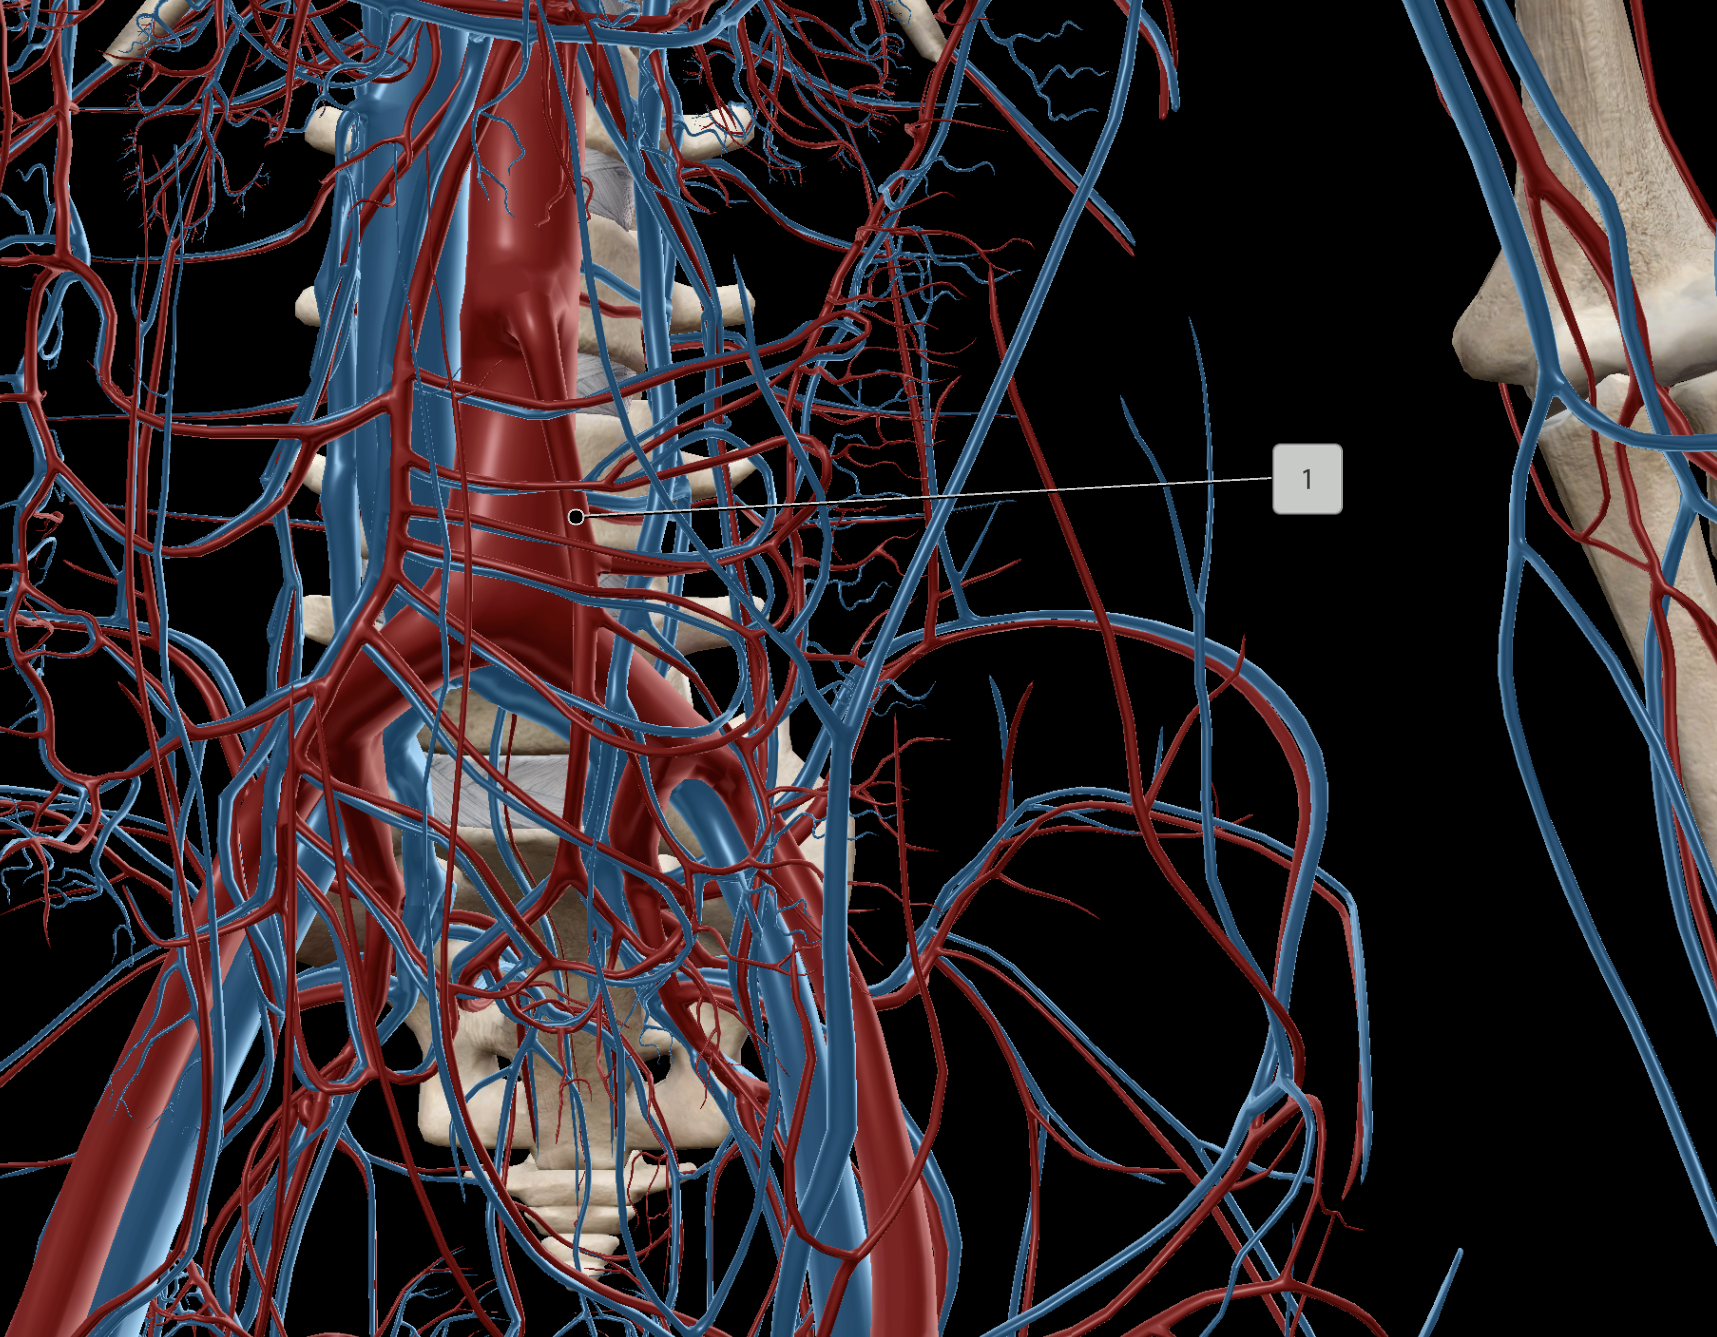

Abdominal Aorta

Superior Mesenteric Artery

Superior Mesenteric Vein

Renal Artery

Common Hepatic Artery

Celiac Trunk